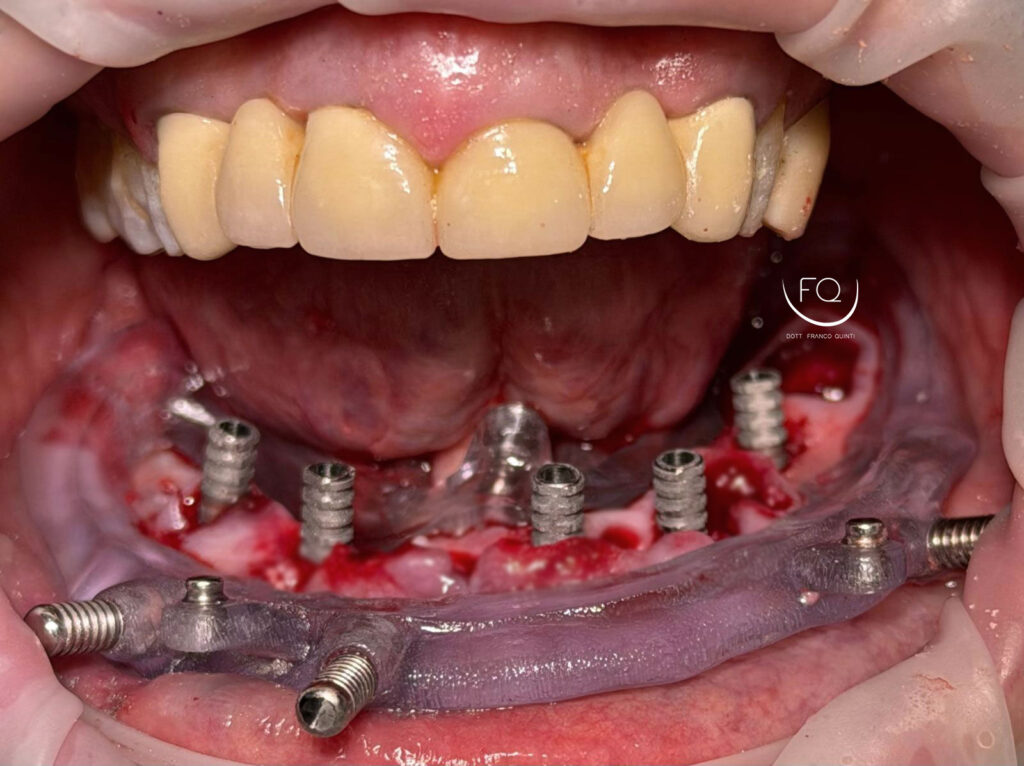

Oggi vi presento un caso di chirurgia computer guidata eseguito con Dima scomponibile.

Dall’immagine iniziale è possibile apprezzare l’estrusione del gruppo incisivo inferiore il quale è stato corretta con la protesi provvisoria a carico immediato stampata in 3D.